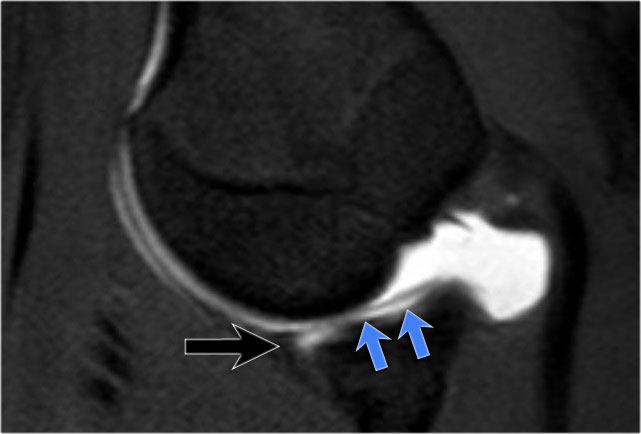

Đây là một bệnh nhân khác có Bankart xương được thấy trên bốn hình ảnh liên tiếp của MRI khớp cản từ ở tư thế ABER.

Lưu ý đường viền bất thường của ổ chảo phía trước và bờ trước bị avulsion (mũi tên)